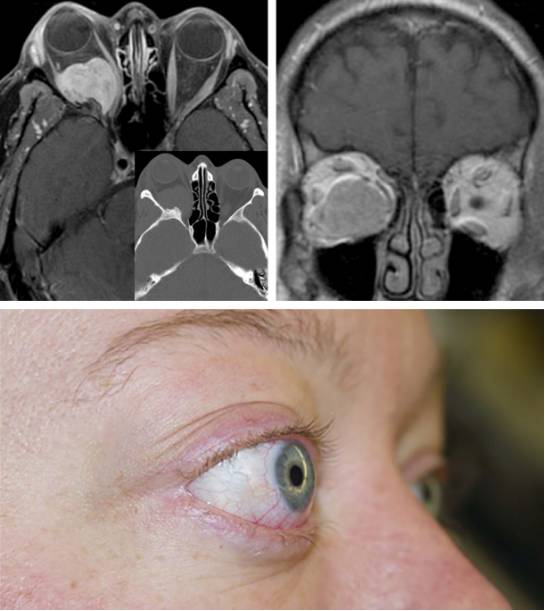

图1. 眶后上部的锥外型神经鞘瘤。可见视神经被内移和眶顶骨质受压侵蚀。

图2. 眼球突出是眼眶肿瘤最常见的症状,图示是一例以此为表现的右眶脑膜瘤,肿瘤的位置及纤维样的质地决定了必须采用眶颧入路进行切除。